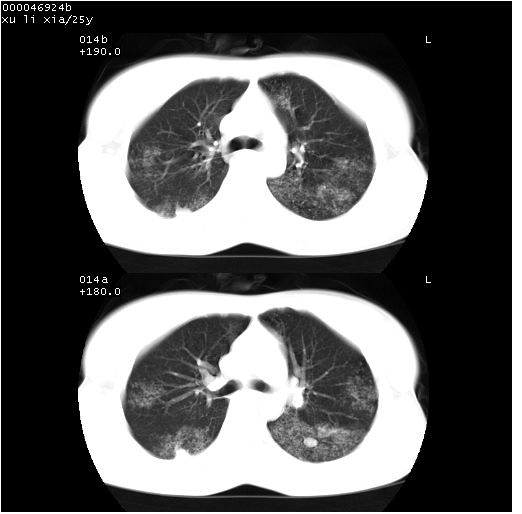

患者 女,25岁。因“左侧卵巢肿瘤”术前胸片偶然发现两肺病变。平素无明显不适,无呼吸系统症状及体征,无传染病史。

cr x线胸片提示:两肺感染性病变(结核可能性大)。

胸部ct轴位平扫(层厚10mm,螺距1.5,重建间隔10mm),图像如下:

(注:上级医院会诊胸部ct片——考虑为肺部真菌感染。)

病灶呈地图样分布于肺外围,与正常组织分界清晰+弥漫性磨玻璃影中见小叶间隔增厚呈碎石路样表现+年轻女性,无明显临床症状=肺泡蛋白沉积症?